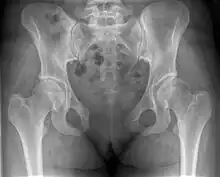

| Post traumatic pubic symphysis diastasis | |

This abnormally wide gap can be diagnosed by radiologic studies such as X-ray, Ultrasound, MRI, CT scan or bone scan. While X-Ray is the gold standard to identify a separation of the pubic symphysis, a decision must be made in regard to which imaging modality to utilize that is patient and case-specific.[3]

X-ray

An X-ray film obtained in the AP view of the pelvic inlet and outlet will show a marked gap between the pubic bones.[3] A normal pelvis will show a gap that is 4–5 mm. However, in pregnancy the hormonal influences cause relaxation of the connecting ligaments and the bones separate up to 9 mm. A gap measuring greater than 10 mm indicates a pathological process.[3]

In addition, a view in the "flamingo stance" can be obtained to demonstrate the instability of the joint. This position consists of the patient standing with weight on one leg and the other bent.[6] A vertical displacement of more than 1 cm is an indicator of symphysis pubis instability.[7] A displacement of more than 2 cm usually indicates involvement of the sacroiliac joints.[3]

A limitation of this imaging study is that X-rays induce radiation and should be avoided during pregnancy.[3]